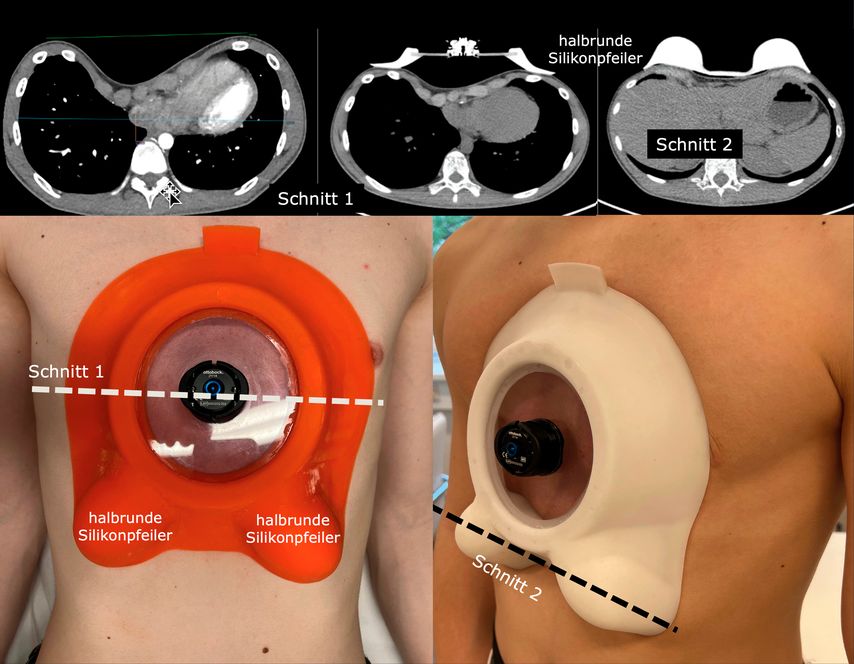

Für die spezielle Situation, in der vorgewölbte untere Rippenbögen („flared ribs“) vorhanden sind, bewährt sich als aktuelle innovative Entwicklung die Y-förmig gestaltete Unterdruck-Überdruck-Saugglocke® (Abb.4), die einerseits den Trichter abflacht, gleichzeitig aber auch eine Kompression auf vorspringende untere Rippenbögen (Abb.5) ausübt und die komplette Umformung provoziert. Alle Saugsysteme machen den Brustkorb grundsätzlich beweglicher.

Die Kompression auf vorspringende Areale der Thoraxwand, wie sie z.B. im Rahmen einer gemischten vertikalen Kiel-Trichterdeformität auftritt, kann durch zusätzliche, individuell angepasste Silikonkissen innerhalb der Saugglocke behandelt werden (Abb.6).